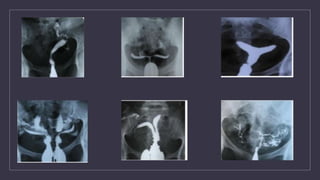

Comment on this picture

How to manage..?

HSG findings in Genital TB

FALLOPIAN TUBES

Specific findings

• Beaded tube

• Golf club appearance

• Pipestem app

• Floral app

• Leopard skin app

Non specific findings

• Hydrosalphinx

• Mucosal thickening

• Peritubal adhesions(tobacco pouch app, loculated spill, cockscrew app